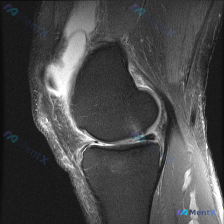

膝关节MRI见大量髌上囊积液但软骨大体完整,提示软骨异常该怎么分析?

今天分享这张膝关节矢状位T2加权MRI的分析,刚好能练一练单关节积液合并软骨信号异常的诊断思路,整理出来和大家讨论。

这是单张膝关节矢状位T2加权MRI,先给大家梳理明确的影像发现:

- 整体影像质量合格,各解剖结构清晰,T2序列信号对比正常

- 骨结构:股骨远端、胫骨近端骨皮质连续,骨髓信号无异常片状高信号,没有明确骨挫伤

- 韧带:前后交叉韧带走行自然,没有明确中断或异常增粗

- 半月板:本次截面半月板形态完整,信号均匀,没有看到穿透关节面的撕裂线

- 明确异常:髌上囊区域可见大量高信号影,提示大量关节积液

- 软骨:股骨髁、胫骨平台关节软骨轮廓连续,没有明确大面积缺损或剥脱性骨软骨炎征象,但临床观察提示存在软骨异常信号改变

拿到这个病例,第一印象是:最突出的异常是大量关节积液,而软骨没有明确的结构性缺损,只有信号层面的异常,这是这个病例最关键的矛盾点。

- 阳性线索:大量髌上囊关节积液,存在软骨信号异常

- 阴性线索:无明确骨挫伤、无韧带断裂、无大面积软骨缺损、无明确半月板撕裂